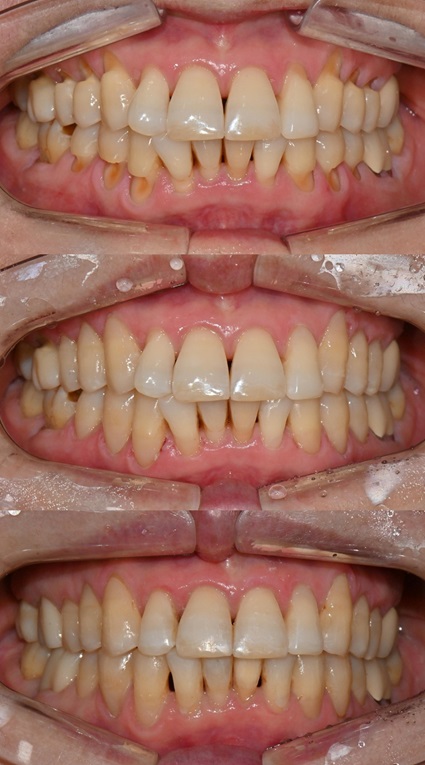

본 환자는 70세 여환으로 가만히 입을 다물고 있을 때 화난 것 처럼 보인다고 해서 튀어나온 앞니를 조금 넣고 싶다는 주소로 내원하셨습니다. 전체적인 치아 및 잇몸 상태를 검진해본 결과, 마모되어 깨진 치아도 있었고, 치경부(치아와 잇몸 사이 경계 부위)가 마모되어 파여 있는 부위도 많았습니다.

2025.2.3. 초진

교정 치료를 시작하기 전에 위아래 깨진 어금니는 보철 치료를 시행하였고, 치경부는 레진 치료를 시행하였습니다. 거의 뿌리의 신경관 근처까지 파여있던 치아가 치경부 레진 치료로 자연스럽게 수복이 되었습니다.

치경부 레진 치료 전후